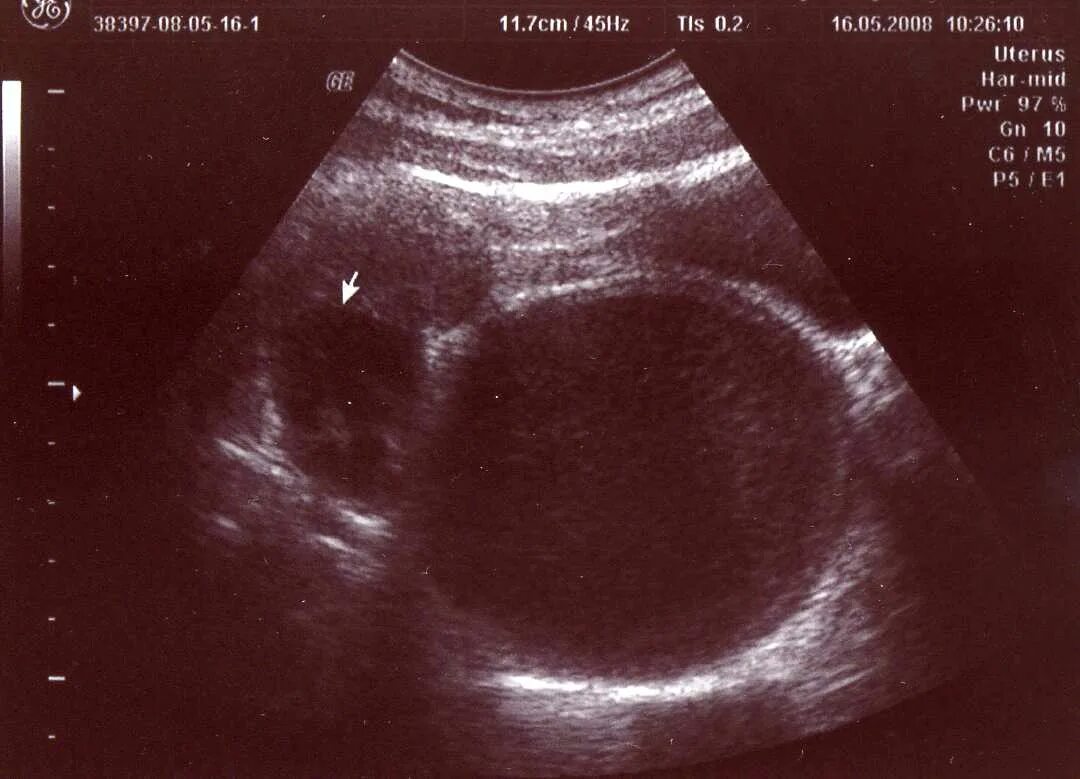

Гематометра симптомы